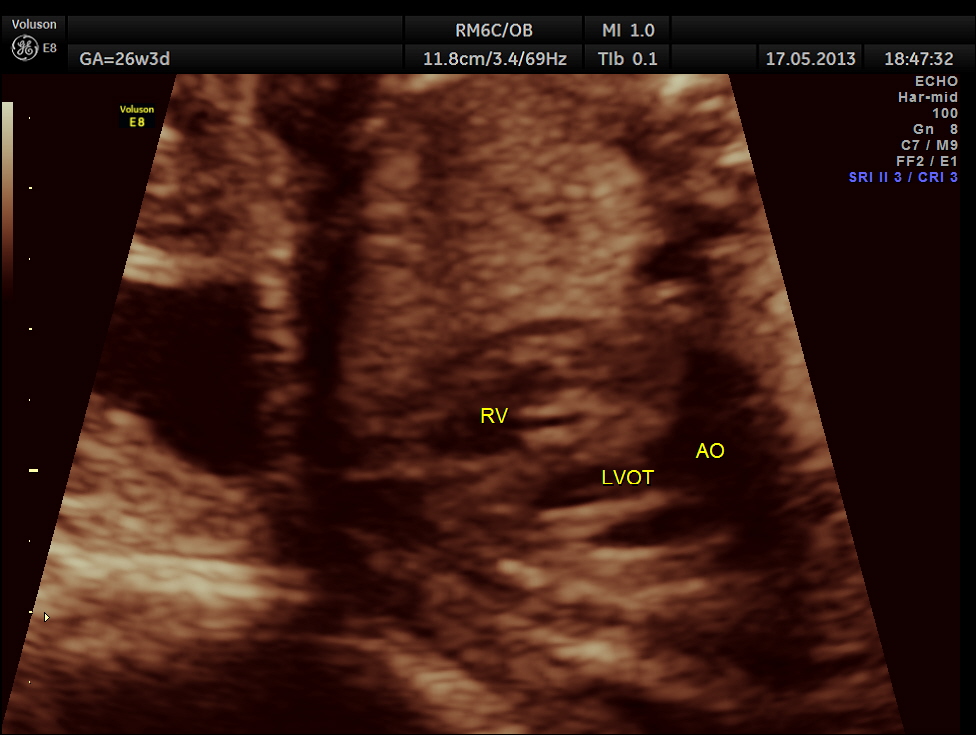

The following images show the sections of the heart.